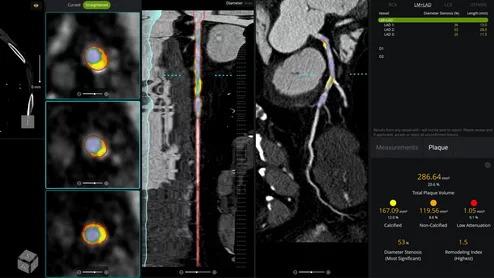

As precision cardiology continues to evolve, the integration of advanced coronary computed tomography angiography (CCTA) and AI-driven analysis is fundamentally changing how we assess and manage coronary artery disease (CAD). Here is a closer look at how Heartflow Plaque Staging is leveraging Total Plaque Volume (TPV) to stratify patient risk.

HeartFlow Plaque Analysis Example

The use of advanced AI software to assess CCTA images continues to gain more momentum.